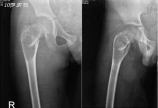

一例儿童股骨近端骨囊肿伴病理骨折的处理策略(EBM分级:专家意见)Senior doctor: Manuel Cassiano Neves MD, MSc (EFORT President 2013-2014)EFORT: European Federation of National Associations of Orthopaedics and Traumatology …………………………………………………………10 y/o boy (otherwise healthy) complaints of R hip pain after falling on the ground, no relevant history previously.PE: R hip limited range of motion with local tenderness.Junior doctor: Which imaging do we need for further differential diagnosis at this moment (3 days after injury)? Is MRI helpful for differential diagnosis with aneurysmal bone cyst at this time?Senior doctor: It looks to me this is a unicameral bone cyst (from the X-ray and CT scan) but as always I like to have a confirmation. For ABC you will see different cavities with liquid inside... but in case it will be difficult to have an MRI I would stay with the CT scan already done.I do not think you need any further image BUT YOU NEED TO DO A BIOPSY AT THE TIME OF SURGERY.Junior doctor:For this kind of cyst lesion, how to do the biopsy? You mean "needle aspiration" with a needle? Can we get a definite diagnosis with biopsy?Senior doctor: Yes usually I aspirate with a needle and if it an exsudate for sure it will be a cyst if it comes blood you have to think about an aneurysmal bone cyst. The treatment for ABC I recommend primarily curettage and bone grafting but with high percentage of recurrence. This is why I treat both lesions in the same way at first attempt.Junior doctor: What’s your treatment plan?Senior doctor: The fracture is in varus and one of the complication will be mal-union or non-union or recurrence of the cyst.So I suggest: Put the child on a fracture table under GA and put the femoral neck in valgus. Do a curettage by a percutaneous incision. Stabilize the fracture with internal fixation. In this particular case where we have a big cyst almost going to the growth plate it is not easy for stabilization. Since is already 10 years of age I would not mind to cross the growth plate... (in the worst scenario you can always make an epiphysiodesis in the contra-lateral side). By crossing the growth plate you will gain better stabilization!Junior doctor: Can we consider internal fixation for this child, if so, which kind of instrument you would like to select?Senior doctor: Definitely in this particular case I will use ELASTIC NAILS and will complement it with an injection of Metilprednisolone according to Campannacci.Junior doctor: Do you think skeletal traction will be just ok?Senior doctor: As I said this fracture is prone to complications so I will definitively would not treat just with traction.Junior doctor: If it is aneurysmal bone cyst, do you still consider ESIN to stabilize/cure it? What's your treatment strategy for aneurysmal bone cyst with fracture?Senior doctor: If it recurrs I will do an open procedure to excise the membrane, use alchool to "burn" the surface, bone grafting and stabilization probably in this case with a special AO plate for the proximal femur (LCP) with locking screws. But I am confident that the ESIN initial approach will be enough (in my experience in this region - 9 cases all healed with this method.Junior doctor: How do you think of the results?Senior doctor: The x-rays look fine to me so let's wait. Just one simple technical note. Since the fracture is very high sometimes I put the 2 nails in the femroal neck instead of one in the trochanteric region... You can also consider using Endcap technique to improve the longitudinal stability like below, but it's up to the surgeon to decide.…………………………………………………………………………………………以下内容由TJPO ZQChen根据文献编译:单纯骨囊肿  自从1876年Virchow首次报道后,单纯骨囊肿逐渐被人们认知。单纯骨囊肿为累及管状骨及扁平骨,并致局部膨胀、菲薄的骨皮质内充满浆液的瘤样病变。80%病例发现于3-14岁儿童,平均年龄为9岁。约占骨骼肿瘤的3%,男:女约为2-3:1。  病理生理:  单纯骨囊肿的病因尚不明确,目前较为认可的病因理论是Cohen提出的骨内静脉回流障碍学说,骨内静脉回流障碍导致骨内高压,增加破骨活性,致局部骨质破坏。  自然史:  单纯骨囊肿最初发生于临近骺板的干骺端,随生长发育逐渐远离骺板。临近骺板的病变常表现出更强的活动性,和远离骺板的病变相比,更容易进展和复发。临近骺板的活动性骨囊肿可能会影响长管状骨的纵向生长。10岁前发病者,囊肿多距骺板较近,可能为活动性的,10岁后发病者,病变多远离骺板,多逐渐转为静止,骺板闭合后骨囊肿很少再进展。  临床表现:  骨囊肿起初常无症状,临近关节可出现疼痛、肿胀及活动受限,发生于表浅骨骼者可触及局部骨骼膨隆、局部压痛,部分病例在发生病理骨折时,或在拍摄X线片时偶然发现。病理性骨折为本病最常见并发症,发生率约66%。部分病例因病变局部受力异常发生肢体畸形。  解剖因素:  单纯骨囊肿可累及管状骨及扁平骨,约94%单纯骨囊肿发生于肱骨及股骨近端,且肱骨发病率比股骨高2-3倍。其他可累及骨还有跟骨(2%)、髂骨(2%)、距骨及胫骨等。发生于扁平骨的病例,年龄多>12-17岁,因其病变部位较深且多无症状,故发现较晚。  诊断方法:  X线片:病变可累及长骨干骺端或骨干,极少累及骨骺,典型病例常表现为局部骨髓腔中心性膨胀,X线透射率增高,周围由薄层骨质包裹,边界清楚,囊肿纵轴常大于其横径,且囊肿横径常小于相邻骺板宽度;除非发生病理性骨折,周围常无骨膜反应。囊肿不会突破骨皮质、层状骨膜反应及Codman三角。  “落叶征”:是多房型骨囊肿的特殊X线表现。当发生病理性骨折时,一侧菲薄的骨皮质断裂形成游离骨块,并坠入囊腔内(常未充满液体),骨块浮于液面,也可部分浸入液体内。多见于骨骼成熟或邻近成熟病例。  CT:通常X线片即可提供诊断骨囊肿的充足信息,但CT扫描有助于评估所有部位的骨囊肿,尤其是骨盆骨囊肿。当囊肿发生于骨干中间或非典型部位时,CT可充分显示病变累及范围。  MRI:典型骨囊肿常表现为均一短T1及长T2信号。但这很难鉴别小于8岁患儿的单纯骨囊肿及动脉瘤样骨囊肿。穿刺取活检:对于年龄<10岁患儿,无论单纯骨囊肿还是动脉瘤样骨囊肿均可穿出血性液体,故穿刺并非诊断单纯骨囊肿的可靠手段。有极少小年龄病例,特别是<5岁者,单纯骨囊肿可突破骺板。  囊肿肉眼观:  囊肿内可为单房,或多个不完整间隔分开的多房囊肿,其间隔被证实为正常骨质。囊腔内充满淡黄色、低粘性的浆液。经分析该浆液内含有前列腺素(特别是前列腺素E),白介素1β及蛋白酶,如胶原蛋白酶等。这些成分可介导增加破骨活性。  鉴别诊断:  动脉瘤样骨囊肿:X线片示病变扩张程度及骨皮质菲薄程度及发病部位可能有利于鉴别,动脉瘤样骨囊肿多为偏心性,常扩张更明显,且囊内可见斑片状或点状钙化。动脉瘤样骨囊肿呈多房性且MRI可显示液-液平面。穿刺囊内为不凝血。患者常有进行性局部疼痛、肿胀。  骨巨细胞瘤:多见于成人。局部痛性肿块为主要症状。病变常见于长骨骨骺。X线片显示为偏心性、膨胀性溶骨性破坏。  骨纤维异样增殖症:股骨颈及肱骨近端纤维异样增殖症继发骨囊肿者并不少见。囊肿周围骨异常膨胀、呈毛玻璃样、囊肿周围硬化骨壳较单纯骨囊肿宽改变利于鉴别。小儿病例常见于多骨型FD。  骨肉瘤:单纯溶骨肉瘤可误诊为骨囊肿。一些骨肉瘤变异或形成假包囊时,较少出现临床症状,影像学表现类似骨囊肿。在影像学上毛细血管扩张型骨肉瘤、Ewing肉瘤也可类似于骨囊肿,但这些恶性肿瘤常表现出更强的侵袭性。  治疗:  治疗的目的在于预防所有可能的并发症及肢体功能障碍。目前单纯骨囊肿尚无统一的首选治疗方法。  单纯植骨:因其较高的复发率(12%-45%),已很少采用。  刮除植骨:行囊内刮除后植骨大大提高了囊肿愈合率,但手术创伤较大,并发症较多,如术中及术后骨折等。  经皮穿刺局部注射激素:最早由Scaglietti报道,其病例成功率可达90%。该方法因其效果可观、操作相对简单、并发症较少,应用较为广泛,但多数病例需反复多次注射直至病灶完全吸收或趋于稳定。该方法是70-90年代治疗肱骨骨囊肿的最流行方法。经皮穿刺自体骨髓移植:近些年,有研究用自体骨髓替代激素作为穿刺注射物,证实自身骨髓对诱导成骨有一定的优势,在一定程度上缩短病程,减少了注射次数。  治疗理念:  通过多因素研究分析证实,影响治疗成功与否的关键因素是患者年龄,无论选择何种治疗方法,>10岁患者成功率(90%)远高于<10岁患者(60%)。  无论治疗与否,在骨骼成熟后,囊肿趋于稳定,但病变部位无法转为影像学正常骨骼。治疗骨囊肿的目标是中止进行性的骨质破坏,获得可正常受力的、功能上稳定的骨骼,而非追求正常的X线表现。有学者认为90%的单纯骨囊肿可保守治疗。  相反,若囊肿累及承重关键部位(如股骨颈、跟骨),且有较高风险发生病理骨折时,或经系列X线片随访证实即将发生病理骨折时应积极手术治疗。  需强调的是,在尝试任何手术或穿刺注射治疗前应确保病理骨折以愈合;但对移位的股骨颈或跟骨后柱病理骨折,可行切开复位内固定以恢复正常血运及解剖完整性以降低远期功能障碍。1.Ulici A, Balanescu R, Topor L, et al. The modern treatment of the simple bone cysts.J Med Life. 2012 Dec 15;5(4):469-73. Epub 2012 Dec 25.2.Norman A, Schiffman M.Simple bone cyst :factors of age dependecy. Radiology. 1997;124:779-782. 3.Conway WF, Hayes CW.Miscellaneous lesion of bone. Radiol. Clin. North Am. 1993;31:339-358.4.Rafath Baig,and John L. Eady. Unicameral (Simple) Bone Cysts.South Med J. 2006 Sep;99(9):966-76.5.Hunt KJ, Bergeson A, Coffin CM, et al. Percutaneous curettage and bone grafting for humeral simple bone cysts.Orthopedics. 2009 Feb;32(2):89.6.A.L. Baert, Leuven,M. Knauth, G?ttingen et al. Imaging of Bone Tumors and Tumor Like Lesions -Techniques and Applications. 2009